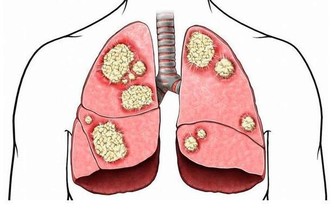

3、突然少尿或無尿

尿酸結晶沉積於腎臟,可導致急、慢性尿酸性腎病和尿石症。大量尿酸結晶沉積在腎小管等處,造成急性尿路梗阻,會突然出現少尿、無尿、急性腎功能衰竭等症狀,所以,一旦出現這類情況,也要警惕尿酸高了。

患高尿酸血症10~2O年的患者,由於結晶長期沉積於腎間質,導致慢性間質性腎炎,可出現夜尿增多、尿比重下降、輕到中度蛋白尿,也就是慢性尿酸性腎病的表現。